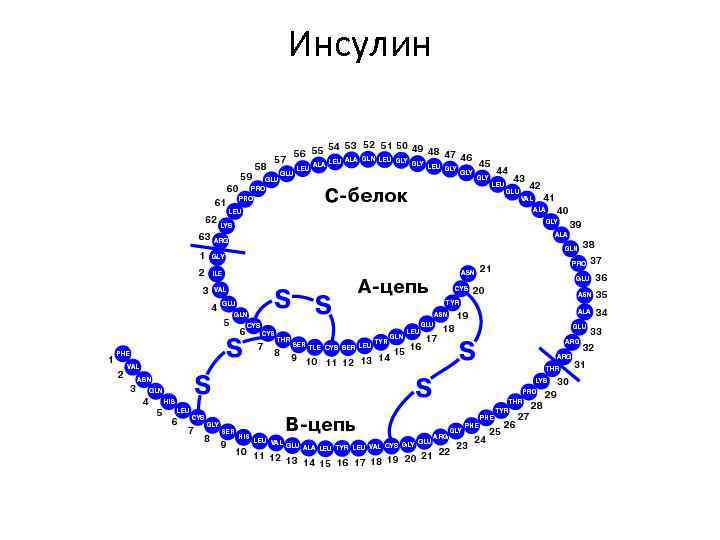

Инсулин

Инсулин

ГОРМОНЫ 1. ИНСУЛИН • СНИЖАЕТ СОДЕРЖАНИЕ ГЛЮКОЗЫ В КРОВИ 2. ГЛЮКАГОН • ПОВЫШАЕТ СОДЕРЖАНИЕ ГЛЮКОЗЫ В КРОВИ 3. СОМАТОСТАТИН • УМЕНЬШАЕТ СЕКРЕЦИЮ ИНСУЛИНА И ГЛЮКАГОНА

ГОРМОНЫ 1. ИНСУЛИН • СНИЖАЕТ СОДЕРЖАНИЕ ГЛЮКОЗЫ В КРОВИ 2. ГЛЮКАГОН • ПОВЫШАЕТ СОДЕРЖАНИЕ ГЛЮКОЗЫ В КРОВИ 3. СОМАТОСТАТИН • УМЕНЬШАЕТ СЕКРЕЦИЮ ИНСУЛИНА И ГЛЮКАГОНА